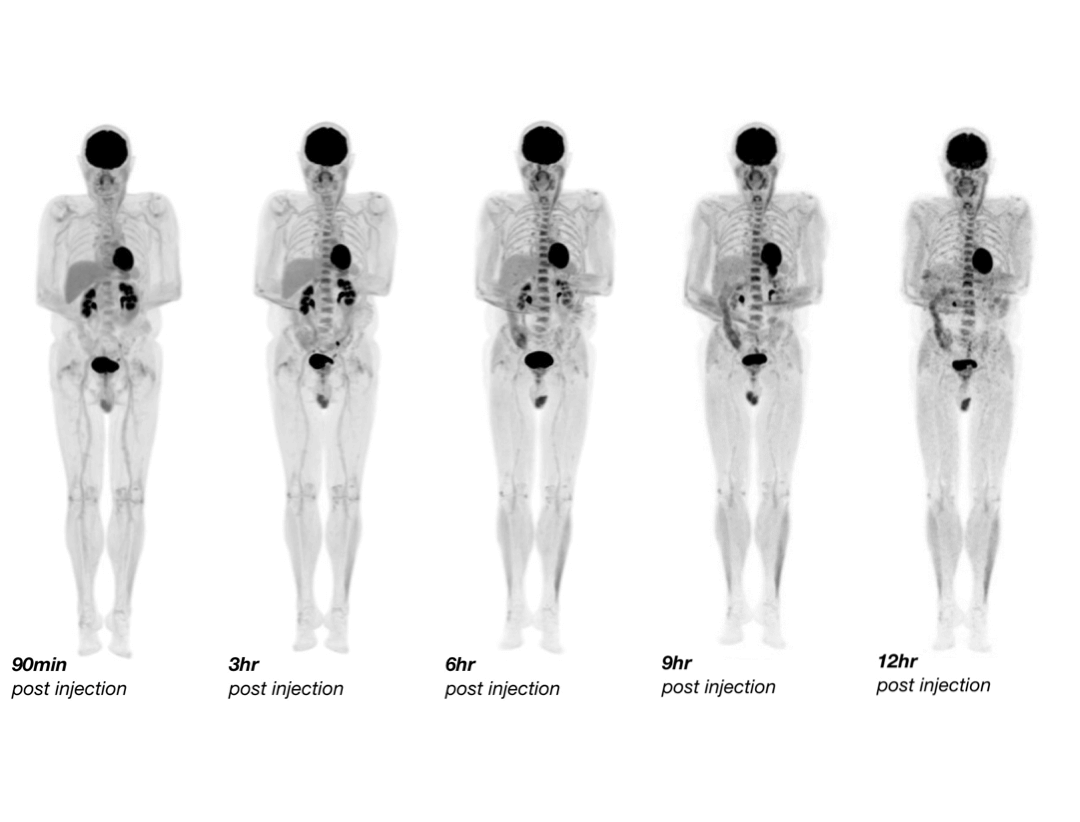

Vizualizarea distribuției radiotrasorului pe perioade extinse

uEXPLORER permite scanări PET/CT realizate până la 6,5 perioade de înjumătățire după injecție, oferind posibilitatea de a urmări distribuția radiotrasorului pe termen lung. Această capacitate sprijină observații clinice detaliate și cercetare avansată.